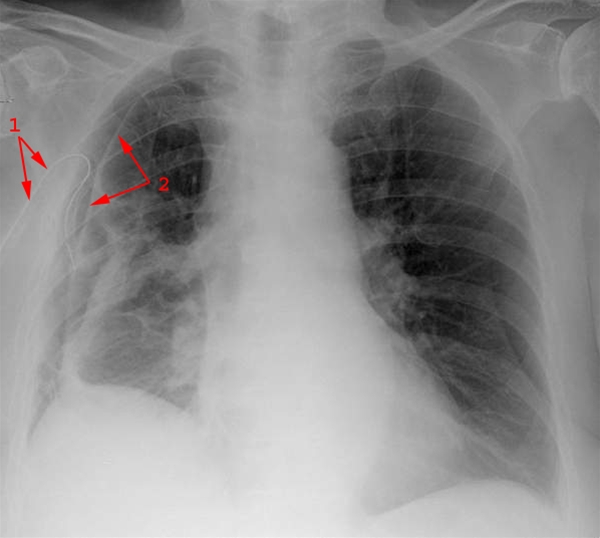

Billedet viser pneumothorax med luftkappe på højre side.

Mellemgulvet er eleveret.

Drænage til pleurahulen (1).

Overfladen af den delvist sammenklappede lunge (2).